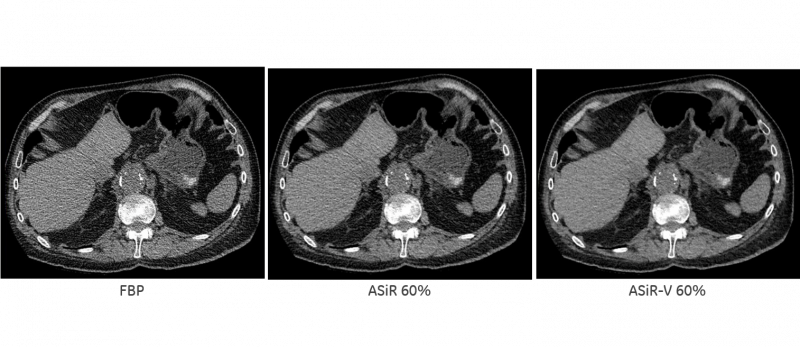

Efficiency and patient comfort both factor into value-based imaging. But it was not the initial reason behind the development of iterative reconstruction. GE Healthcare originally planned to market Adaptive Statistical iterative Reconstruction (ASiR) as the means for improving image quality. The latest version of ASiR is being positioned for its ability to significantly reduce patient radiation dose during CT exams while achieving a reconstruction speed similar to that of conventional analytical reconstruction using filtered back projection. (Graphic from GE Healthcare Image Gallery)

Opportunism has been the de facto marketing model for original equipment manufacturers. OEMs have tended to develop and make what their engineers have shown was possible, then wrapped those developments in what the market demanded. Iterative reconstruction (IR) is an example. First positioned as a way to improve CT image quality, IR was later — and to this day continues to be — marketed as a way to reduce radiation dosage while maintaining image quality.